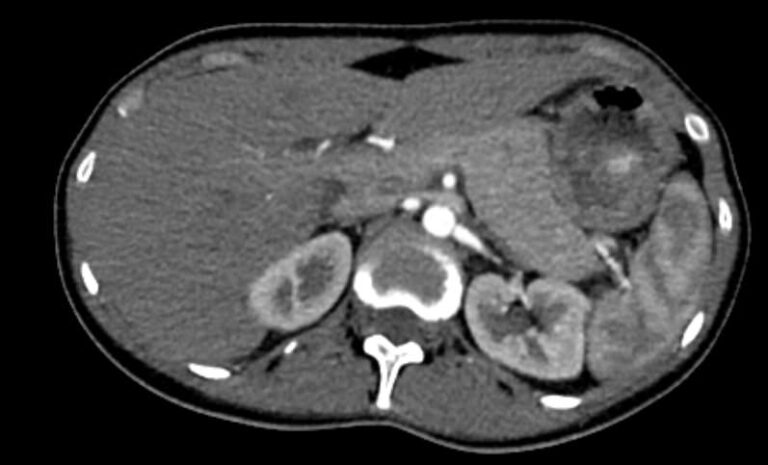

Мультиспиральная КТ сосудов почек (КТ-ангиография) с внутривенным болюсным контрастированием проводится для диагностики патологии почечных артерий. С помощью КТ-ангиографии можно выявить врожденные аномалии развития сосудов почек, диагностировать стенозы (уменьшение просвета) почечных артерий за счет развития атеросклеротических бляшек.

КТ сосудов почек применяется для выявления признаков вторичной артериальной гипертензии, при планировании оперативных вмешательств и для оценки успешности проведенной операции на сосудах. КТ ангиография почечных артерий позволяет оценить их анатомию, выявить добавочные и аберрантные почечные сосуды, определить типично ли они распространяются в ворота почки или заходят в паренхиму через корковый слой.

Чувствительные детекторы улавливают рентгеновские лучи после их прохождения сквозь тело человека. На основании этих данных получаются изображения сосудистой системы почек в мельчайших подробностях. Кроме того, с помощью цифровой обработки данных томограф реконструирует трехмерные модели кровеносных сосудов на уровне исследуемой области. 3D-реконструкции помогают увидеть пространственное соотношение анатомических структур и значительно повышают качество диагностики.

В наших медицинских центрах КТ-ангиография почечных артерий выполняется на новейших мультиспиральных компьютерных томографах экспертного класса TOSHIBA AQUILION. Аппараты сканируют область почек, производя одномоментно множество послойных срезов исследуемой зоны, благодаря этому создаются изображения кровеносной системы высокого качества. Это позволяет проводить точную и достоверную диагностику патологии почечных артерий. При этом за счет скоростного мультисрезового сканирования пациент получает минимальную дозу рентгеновского облучения.